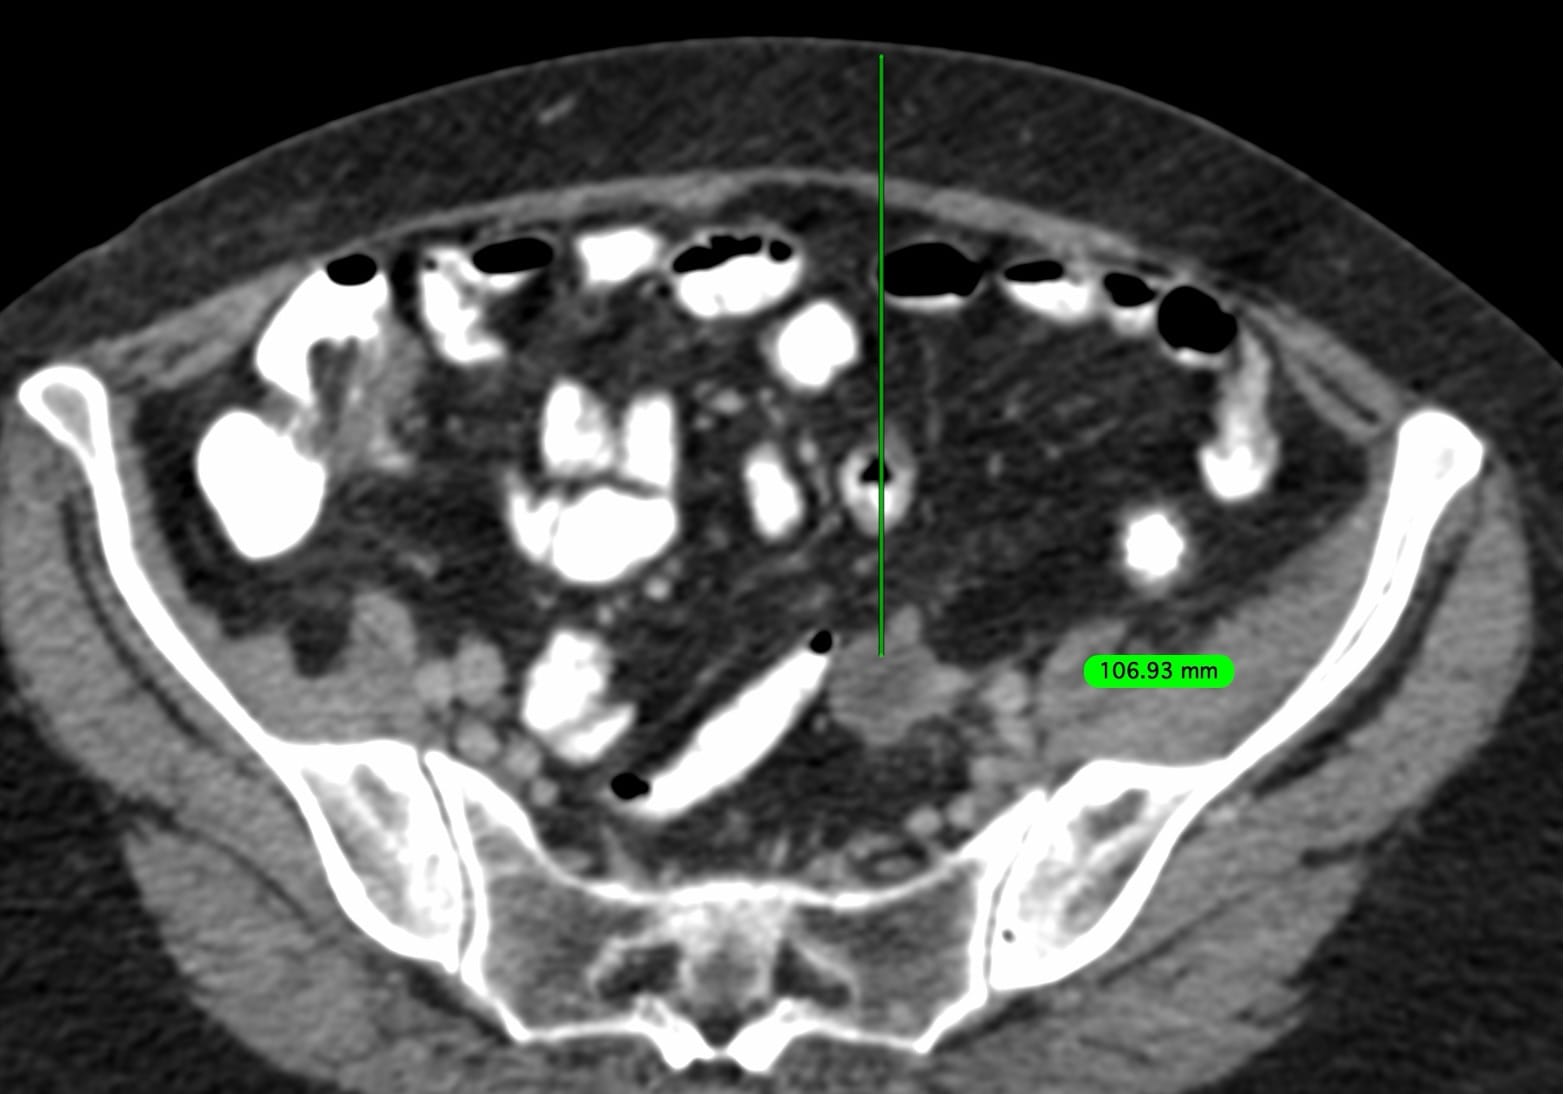

A 69-years old treated earlier for carcinoma ovary and endometrium, presented with new mesenteric nodules/nodes.

The oncologist wanted a biopsy.

This node/nodule and approach seemed to be the best bet.

The video describes the case, the use of the blunt-tip to bypass the bowel without going transbowel and the ease with which these lesions can be targeted.